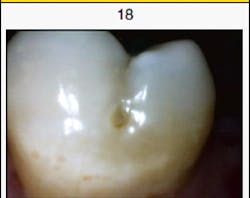

A 43-year-old male patient presented for a routine recare exam with a deep pit and staining on the buccal surface of No. 18 (figure 1). When we examined this tooth clinically, we were unsure about whether to attempt remineralization on this tooth or treat it with a small direct restoration. We decided to perform a quick scan with the Canary System by Quantum Dental Technologies. The Canary System uses a laser and heat (photothermal radiometry and modulated laser luminescence technology) to penetrate the tooth by up to 5 mm and measure the organization of the crystallization within the tooth (3). This area of concern received a Canary Score of 45. On the Canary Scale, a score of 0–20 indicates healthy tooth structure, 21–70 indicates early decay, and 71–100 indicates advanced decay (4).